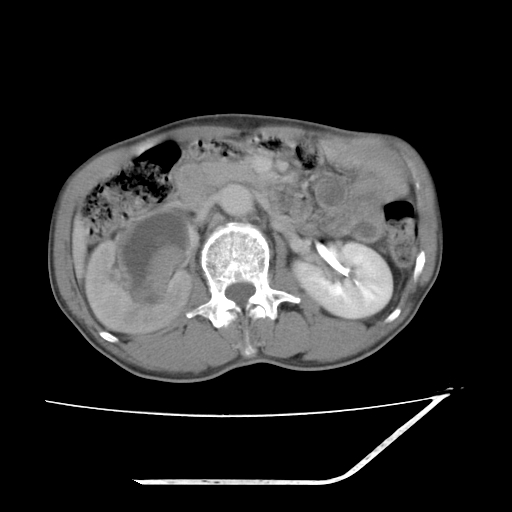

增强

考虑右肾盂癌,肾动脉受侵,右肾功能减退,右肾盂输尿管积水,管壁增厚,考虑种植转移,应该把下面扫完的

支持右侧肾盂癌伴肾静脉瘤栓形成可能性大,右肾结石.肝右叶后段低密度影,不除外转移.

考虑右肾盂癌,肾动脉受侵,右肾功能减退,右肾盂输尿管积水,管壁增厚,考虑种植转移  支持

右肾囊实性占位,支持肾癌,窗宽窗位不是很理想

右肾盂旁ca并肾静脉瘤栓形成/肾功能降低。

右肾结石。

右肾盂癌,肾动脉受侵,右肾盂输尿管积水,管壁增厚,考虑种植转移

支持 右侧肾盂癌伴肾静脉瘤栓形成可能性大,右肾结石;肝右叶后段低密度影,不除外转移。

1.右侧肾盂癌伴肾盂积水。

2.肾脏功能减退,原因有:(1)肾动脉受侵。(2)肾静脉受侵(3)肾积水,等。本例,肾动脉显影较好,但受压明显;肾静脉无明显显示,受压或静脉癌栓,下腔静脉腔内未见明显充盈缺损。

3.右侧上段输尿管扩张,原因:(1)积水所致;(2)种植。